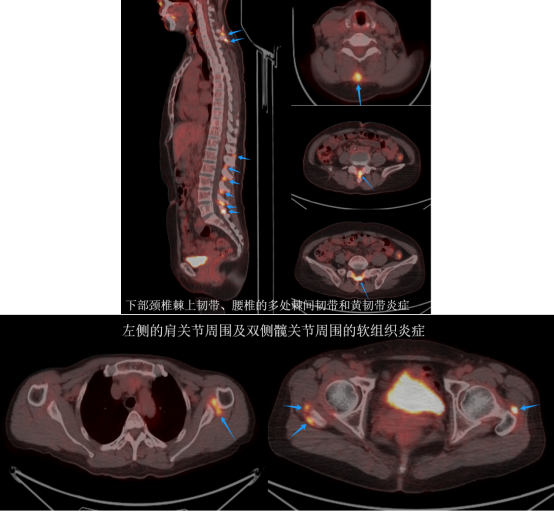

经过仔细的分析,医生们得出了结论:彭女士头部左侧侧脑室旁、双侧侧脑室室膜下多发大小不等的钙化结节,双肺多发磨玻璃结节及实性结节影,符合肺多发小结节样肺泡细胞增生的特征;同时,她的颅骨、胸骨、脊椎、骨盆骨等等多处存在骨质增生硬化的改变,双肾多发囊肿,左侧肾上腺存在结节。然而,这些病变在PET/CT图像上均未显示出葡萄糖代谢的异常增高,这意味着这些病变很可能并非恶性病变的多发转移。

至于彭女士腰背部和肩关节周围的疼痛,PET/CT影像给出了明确的解答:这些疼痛源于多部位的软组织炎症,与结节性硬化症无关。接下来,彭女士需要进一步结合临床检查,排查是否存在风湿免疫性因素,并进行相应的治疗以缓解疼痛。